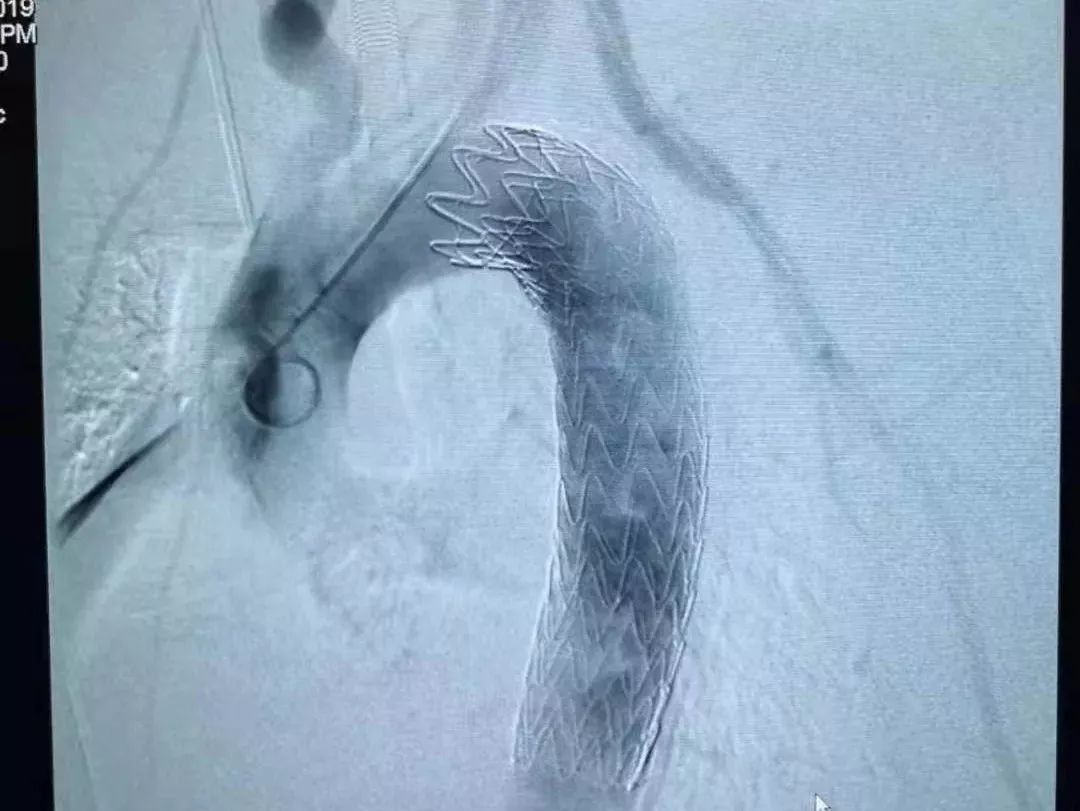

手术台上,专家团队判断很有可能是由于食道的蠕动,或是主动脉内血流的强劲冲击,这根鱼刺已经穿出食管进入胸腔甚至主动脉了。

此时已经没有微创取刺的可能了,必须尽快开胸探查将鱼刺取出。

手术方案立即调整。医生从右侧开胸探查胸腔,发现鱼刺果然是穿出了食管,几乎整个扎进了主动脉内,仅在外露出3毫米的刺尖。